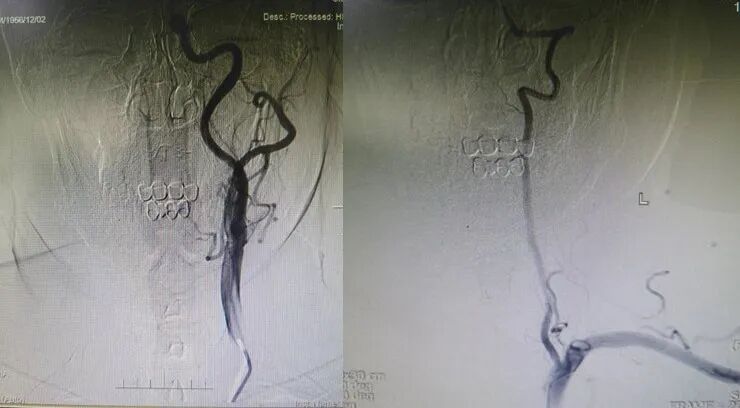

入院影像检查

导丝怎么扩【载药时代 球扩天下】NOVA DES®颅内药物洗脱支架在症状性颅内动脉狭窄中的应用—烟台鲁东医院使用体会二例!_https://www.jmylbn.com_新闻资讯_第19张

重要影像结论:右侧颈内动脉C6段重度狭榨。

重要影像结论:右侧颈内动脉C6重度狭窄(90%)。

诊断

主要诊断:右侧颈内动脉C6段重度度狭窄

病变部位:右侧颈内动脉C6段

远端正常血管直径(mm):3.1

狭窄处最小直径(mm):0.5

病变长度(mm):10

狭窄度(%):90%以上

治疗中影像

导丝怎么扩【载药时代 球扩天下】NOVA DES®颅内药物洗脱支架在症状性颅内动脉狭窄中的应用—烟台鲁东医院使用体会二例!_https://www.jmylbn.com_新闻资讯_第20张

导丝怎么扩【载药时代 球扩天下】NOVA DES®颅内药物洗脱支架在症状性颅内动脉狭窄中的应用—烟台鲁东医院使用体会二例!_https://www.jmylbn.com_新闻资讯_第21张

导丝怎么扩【载药时代 球扩天下】NOVA DES®颅内药物洗脱支架在症状性颅内动脉狭窄中的应用—烟台鲁东医院使用体会二例!_https://www.jmylbn.com_新闻资讯_第22张

导丝怎么扩【载药时代 球扩天下】NOVA DES®颅内药物洗脱支架在症状性颅内动脉狭窄中的应用—烟台鲁东医院使用体会二例!_https://www.jmylbn.com_新闻资讯_第23张

术后影像及检查

影像结论:血管成形良好,支架贴壁良好,远端显影良好。